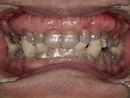

症例紹介(50代男性)

治療前の口腔写真。下顎後退により気道が狭くなっている様子